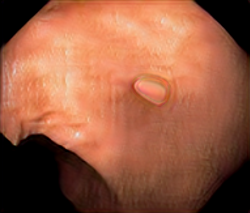

We have used a polyp dataset published with HyperKvasir dataset [51], which consists of polyp findings extracted from endoscopy examinations. HyperKvasir contains polyp images with corresponding segmentation masks annotated by medical experts. We use only this polyp dataset as a case study because of the time and resource-consuming training process of the SinGAN-Seg pipeline. However, the SinGAN-Seg model and pipeline can be used for any segmentation dataset.

A few sample images and the corresponding masks of the polyp dataset in HyperKvasir are shown in Fig 2. The polyp images are RGB images. The masks of the polyp images are single-channel images with white () for true pixels, which represent polyp regions, and black () for false pixels, which represent clean colon or background regions. In this dataset, there are different sizes of polyps. The distribution of polyp sizes as a percentage of the full image size is presented in the histogram plot in Fig 3, and we can observe that there are more relatively small polyps compared to larger polyps. Additionally, a subset of this dataset was used to prove that the performance of segmentation models trained with small datasets can be improved using our SinGAN-Seg pipeline, and the whole dataset was used to show the effect of using SinGAN-Seg generated synthetic images instead of a large dataset which has enough data to train segmentation models. In this regard, this dataset was used for two purposes: